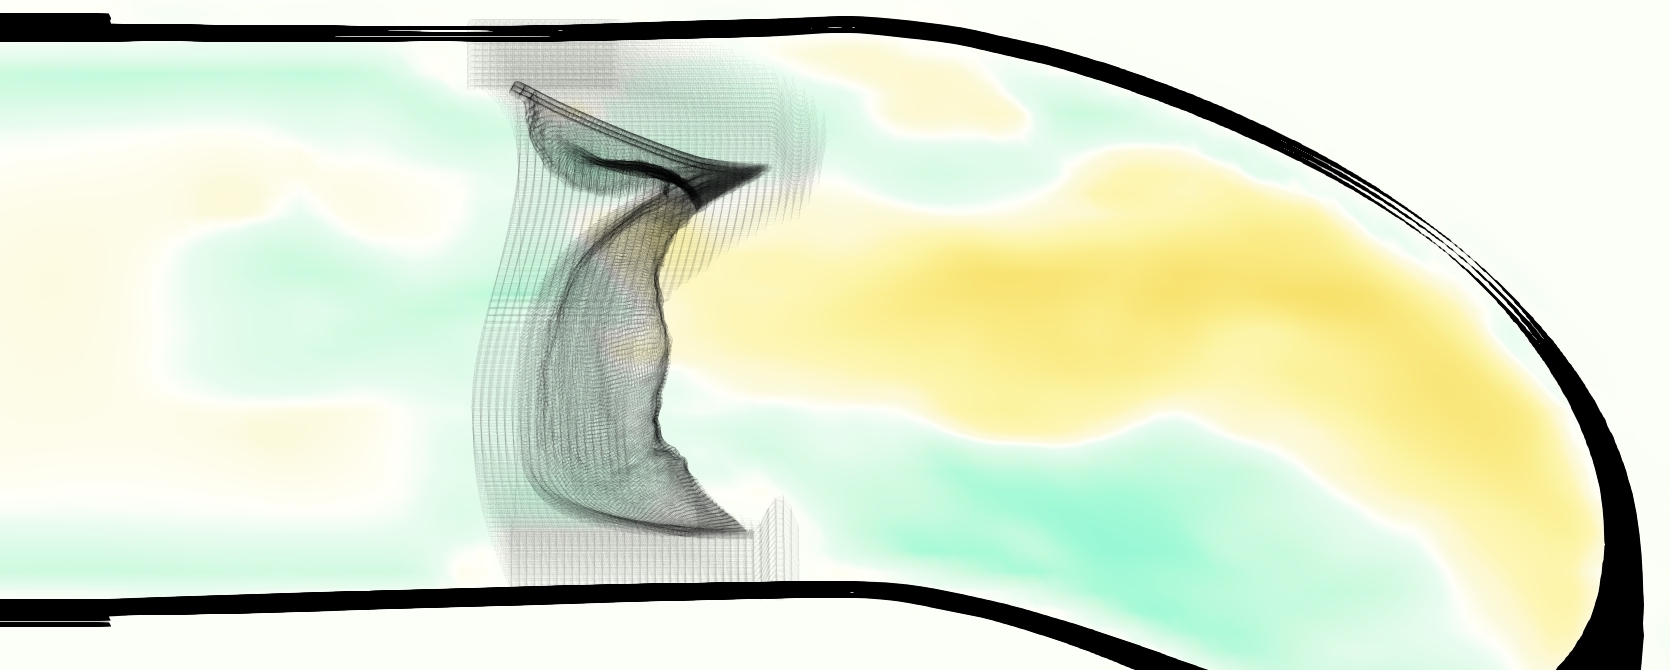

Slice views of the (axial) component of fluid velocity in the axial plane, orthogonal to the flow direction, show that the simulation replicated the development of the jet over the cardiac cycle. At each phase, the simulation matched the forward speed of the core of the jet and the locations of reverse flow back towards the valve annulus. While there are some differences in the shape of the jet at certain phases and locations, the simulation clearly produced the general dynamics of the cardiac cycle that are seen in the experiment.

At = 0, the axial slice directly at the valve annulus shown in columns 1 and 2 in Figure 6, there was excellent agreement between the simulation and experiment over the cardiac cycle in the speed and shape of the jet through the valve. In both cases, the axial velocity increased as the flow accelerated during systole and the valve leaflets opened, then decreased during diastole with slight negative velocity before the valve leaflets were fully closed. The forward flow through the valve annulus did not form a full circle, but rather developed a triangular shape with a point of the triangle forming along the interior curve of the vessel, at the bottom of the axial slices. At = 0, the points of this triangular jet shape aligned with the commissures of the valve. This shape persisted during peak systole and was well-matched by the simulation.

The axial slice = 0.625 cm, shown in columns 3 and 4 in Figure 6, cut through the support scaffolding of the valve and the leaflets when they are open. In the experimental data, the shape of the jet changed as it moved downstream. A triangular shape occurred, but the points were then aligned with the middle of each open leaflet as opposed to the commissures. Those points were also more rounded than they were at = 0. The peak velocity of the jet was faster at = 0.625 cm than at = 0, as the flow accelerated through the open valve leaflets. The simulation produced these features at = 0.625 cm. The triangular shape of the jet shifted similarly, and its speed increased compared to the upstream slice. As the flow decelerated into diastole, the jet shape remained roughly triangular but diminished in intensity before disappearing after valve closure.

The jet continued to develop at = 1.25 cm, an axial slice immediately downstream of the valve scaffolding and open leaflets, shown in columns 5 and 6 in Figure 6. In the experimental data, the points of the triangular jet shape extended further towards the vessel wall. In addition, regions of reversed flow developed in the locations downstream of the commissures, resulting in curved sides to the shape of the jet. Each tip of the jet was unique, due to variations in the individual leaflets in the physical bioprosthetic valve. These variations are apparent in the velocity fields, possibly because the jet edges are similar enough cycle to cycle that irregularities are still being captured even with phase averaging. Further discussion of these features can be found in Schiavone et al. [39], which showed that the jet tip shapes occurred in different pulmonary anatomies, demonstrating that they were likely due to inherent properties of each leaflet. The leaflets in the mathematical model of the valve are identical, so these nuances in leaflet variation could not be replicated. The simulation did capture some of the extension of the tips of the jet, as they were closer to vessel wall at slice = 1.25 cm than = 0.625 cm. The curves in the triangular sides of the jet were also present in the simulation, though they were less pronounced than the experimental data. At both = 0.625 cm and = 1.25 cm, the jet shape in the simulation was smoother than the jet in experiment. It is possible that the free edges of the leaflets in the mathematical model are not fully replicating the behavior of the physical leaflets of the bioprosthetic valve, in particular the amplitude or frequency of leaflet flutter, leading to the variations seen in the jet shape at = 1.25 cm downstream of the leaflet edges. The simulation, however, does capture the key features of the triangular shape and speed of the jet. Overall, qualitative comparisons demonstrated that the simulation reproduced key features of the flow during systole and diastole.